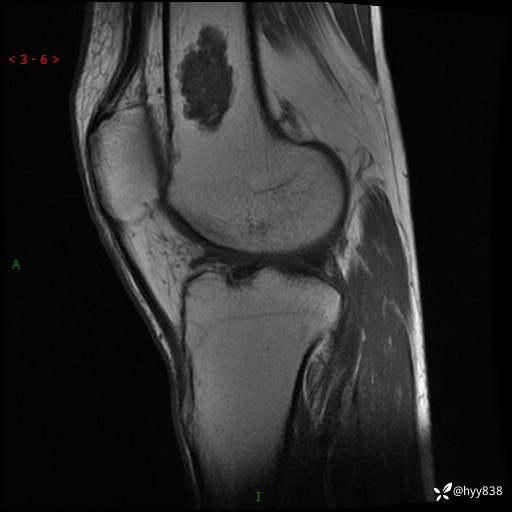

患者性别:男

患者年龄:60岁

主诉:右大腿疼痛不适数月

膝关节平片

MRI

内生软骨瘤 (27)